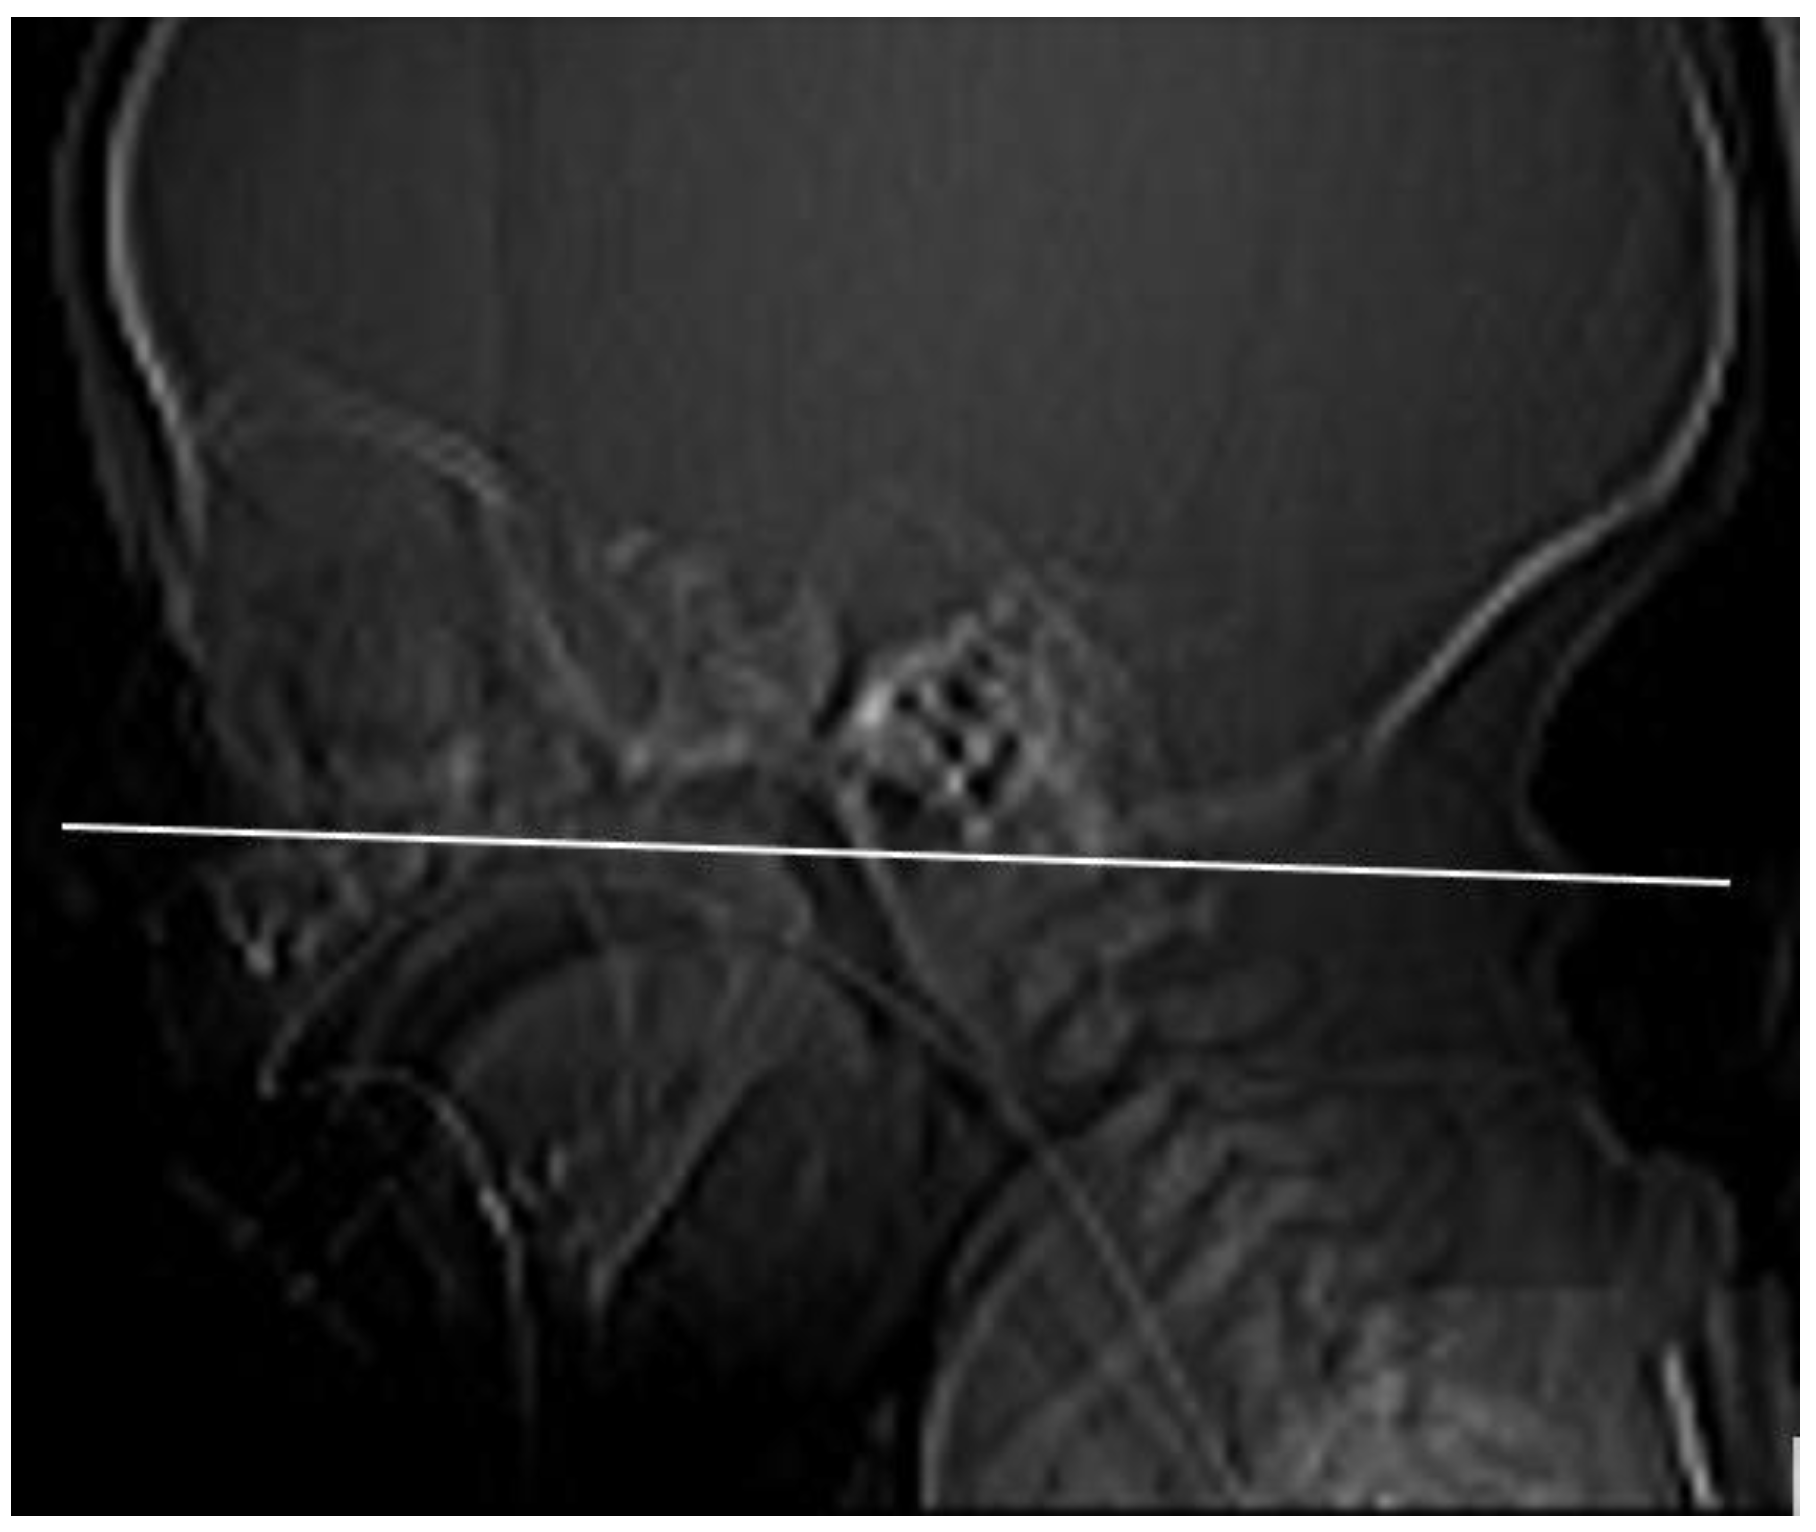

We have evaluated the nasal cavity CT imaging of 24 pediatric patients diagnosed with ICD-10: Q30.0 choanal atresia examined at the Department of Pediatric Otorhinolaryngology of the Medical Faculty of the Comenius University and the National Institute of Children’s Diseases in Bratislava (Slovakia). We have recorded the sex of patients, the presence of syndromes, their age at the time of the nasal cavity CT examination, and the types of atresia (congenital–acquired, unilateral–bilateral). In the case of the unilateral atresia, we have examined which half of the nasal cavity was affected. We determined the character of the atretic plate (membranous, bone-membranous, and bone types) and their locations (unilateral, bilateral) [4]. Using the method of Slovis et al. (1985) [10], a CT section paralleling the posterior hard palate at the level of the pterygoid plates was obtained in all children (Figure 1). The sections were 0.5 to 1 mm thick. The TomoCon PACS system was used for CT scanning. The measurements were obtained by one examiner with Tomocon Viewer application measuring tools.

Figure 1. The measurement plane: CT section paralleling the posterior hard palate at the level of the pterygoid plates.